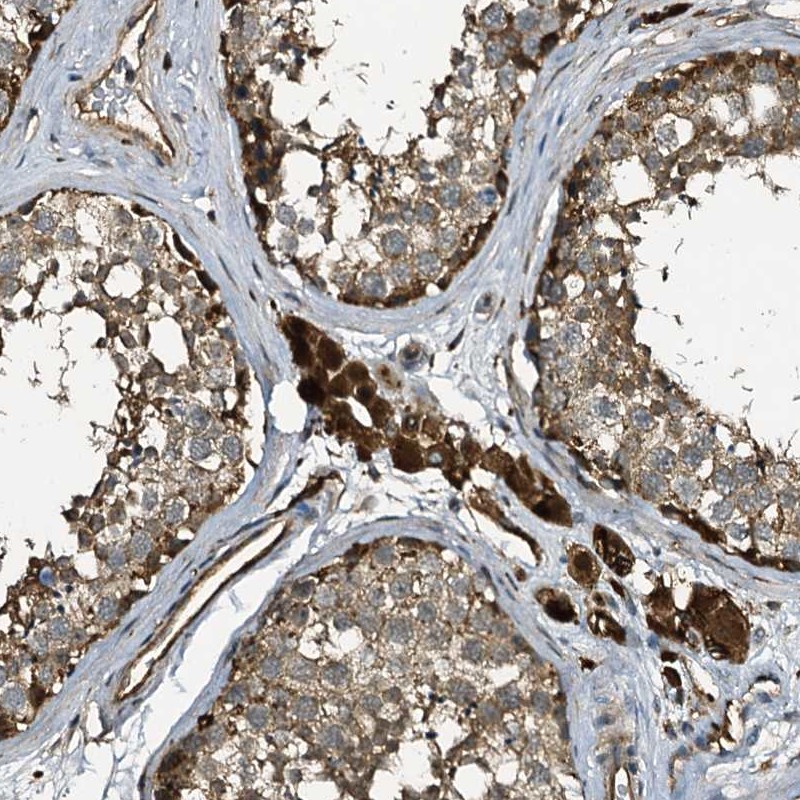

Immunohistochemical staining of human testis shows strong cytoplasmic positivity in Leydig cells.